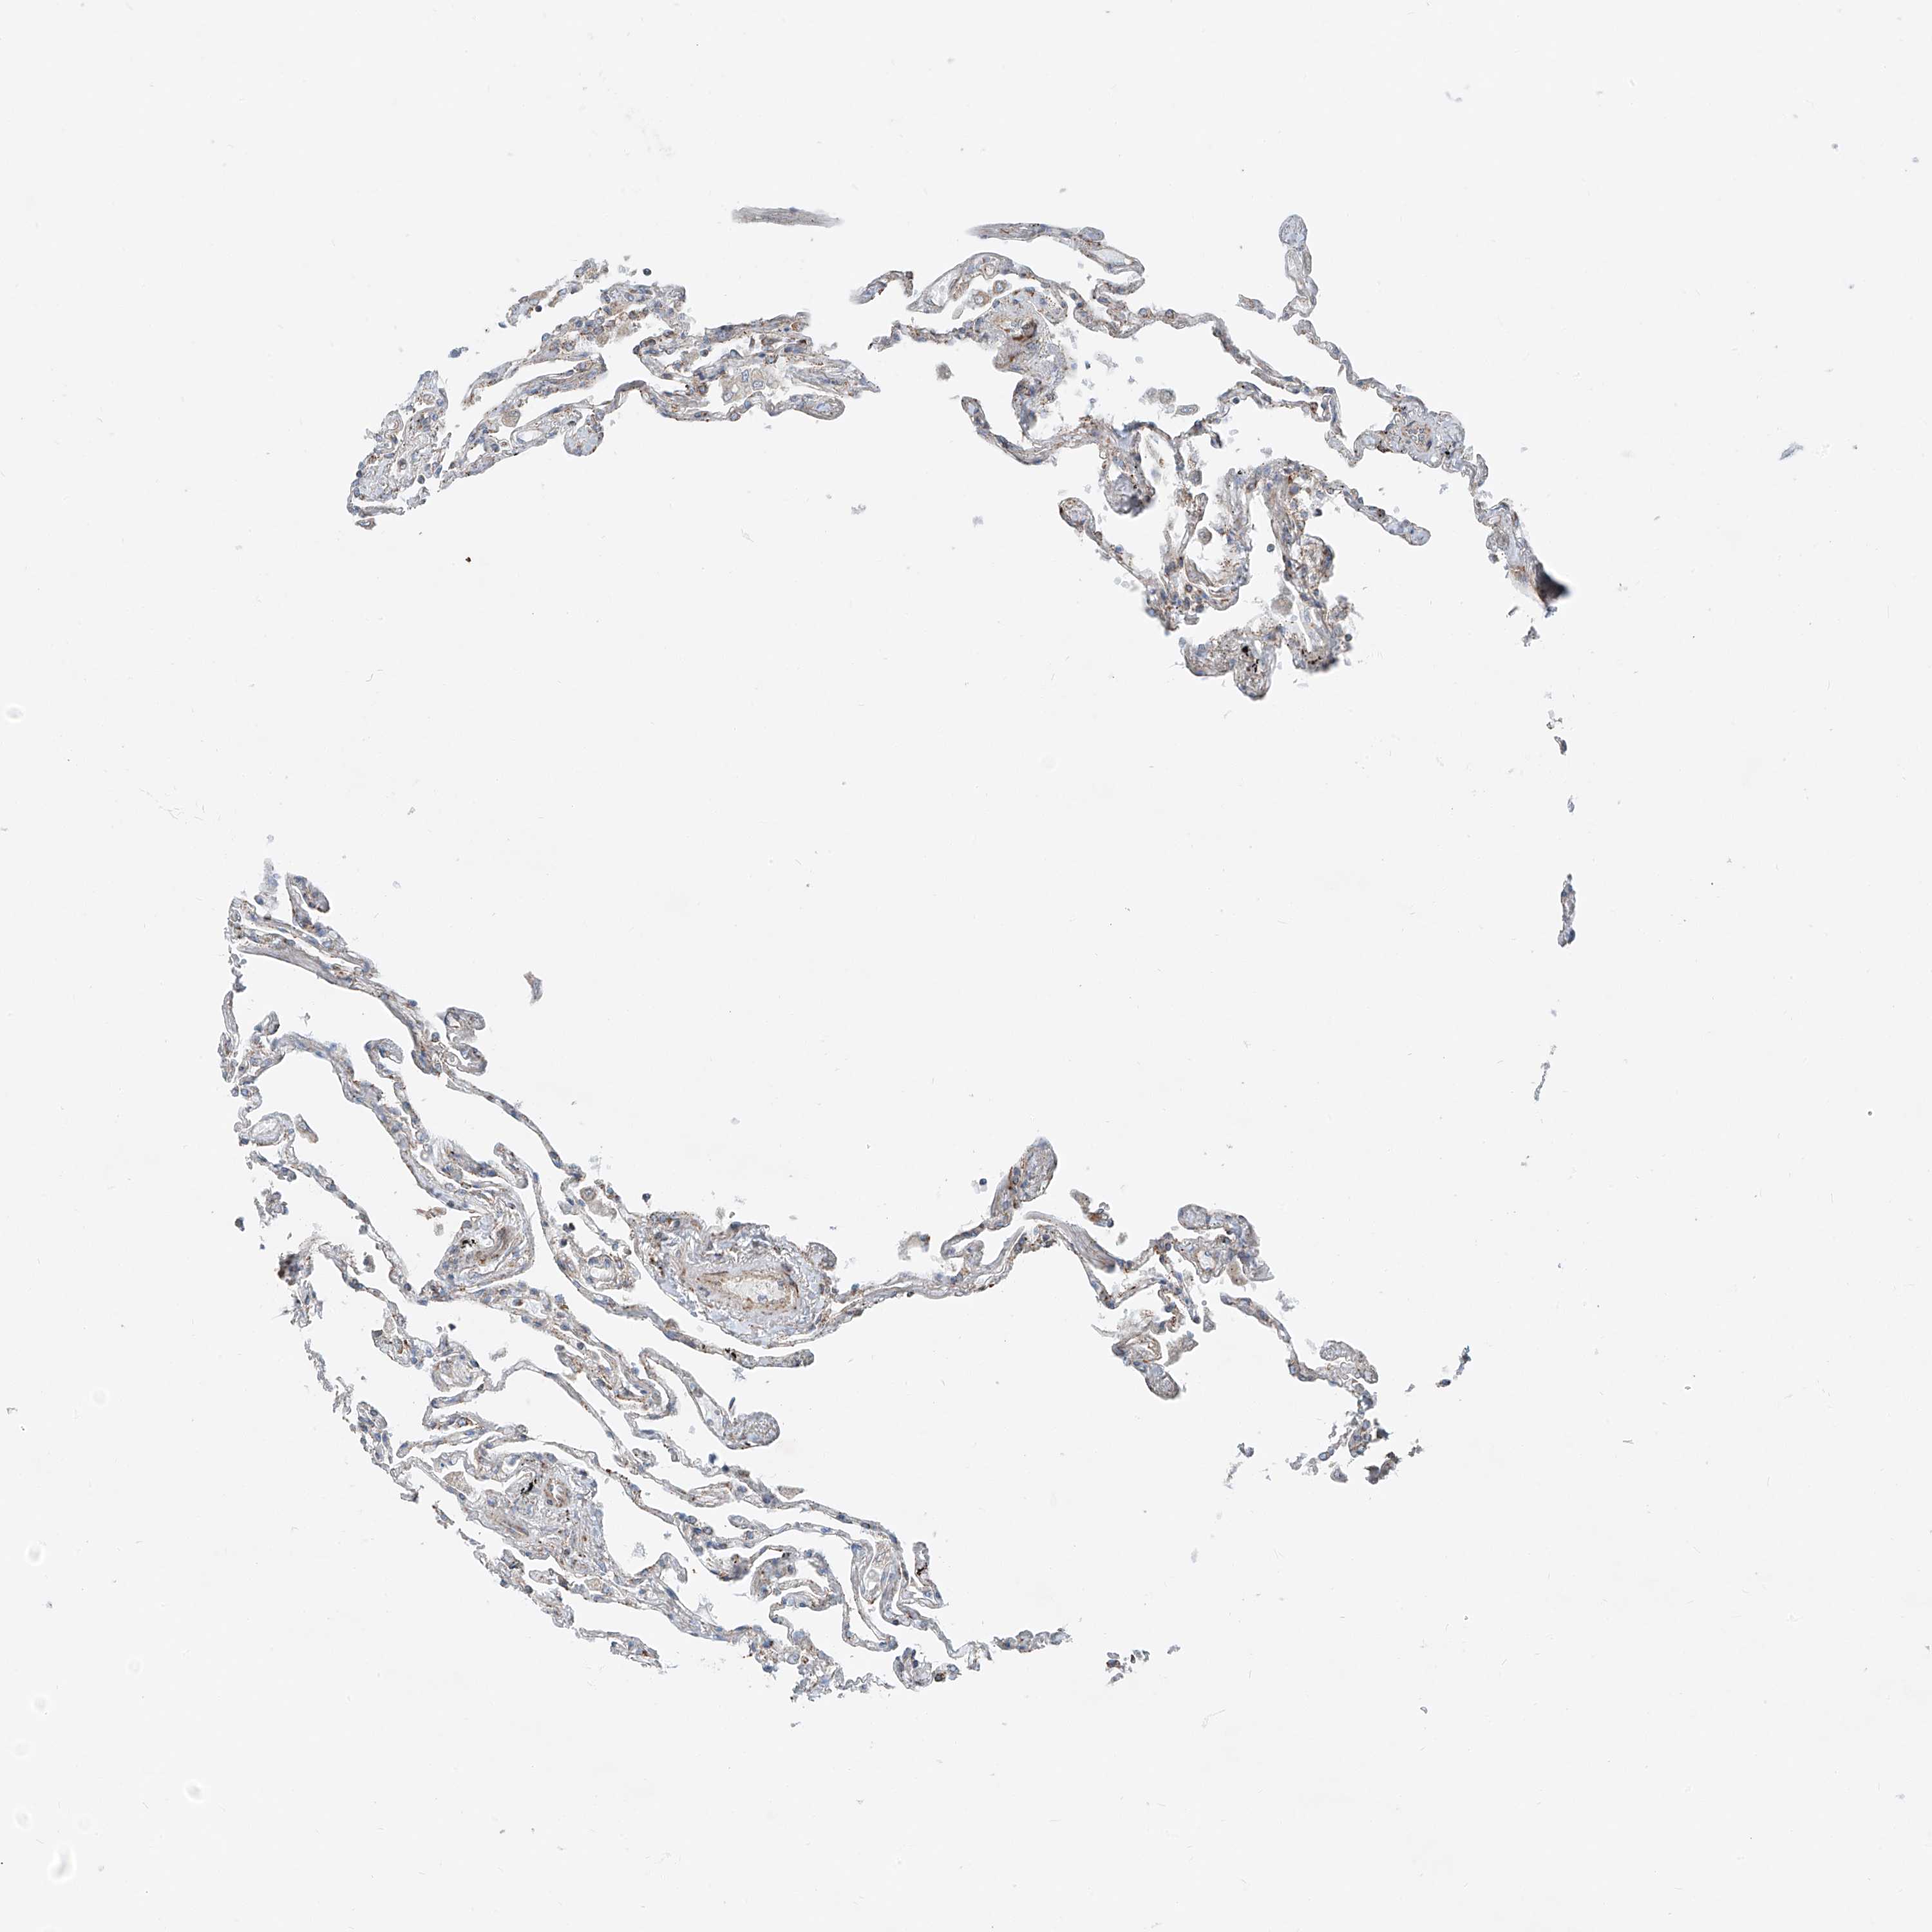

LUNG